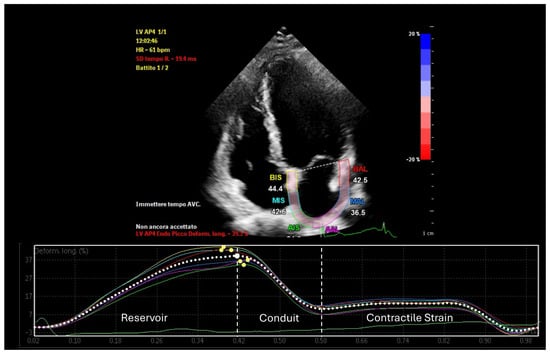

Left atrial strain, measured using speckle-tracking echocardiography, has emerged as a valuable tool for non-invasive assessment of atrial function. This technique evaluates myocardial deformation, dividing the imaging results into three phases: reservoir strain, conduit strain, and booster strain (Figure 1) [8]. Strain imaging enables early detection of atrial dysfunction before structural abnormalities become apparent, facilitating timely intervention and risk stratification [9]. This review examines the interplay between LA-EAT and atrial remodeling, emphasizing the clinical utility of atrial strain analysis in screening, management, and prognosis.

Figure 1.

Phases of left atrial strain in a healthy subject.

Left atrial strain assessment encompasses three main components:

- Reservoir function (positive strain): Peak atrial longitudinal Strain (PALS) measures the atrial expansion during ventricular systole, when the atrium fills with blood from the pulmonary veins, reflecting atrial compliance and the ability to accommodate pulmonary venous return. Reduced reservoir strain is indicative of impaired atrial compliance, which can result from increased EAT-induced fibrosis or inflammation.

- Conduit function: This assesses the atrium’s role as a conduit during early ventricular diastole, reflecting its capacity to passively transfer blood from the pulmonary veins to the left ventricle. Decreased conduit strain suggests early atrial stiffening or impaired ventricular filling, conditions often exacerbated by EAT-related paracrine dysfunction.

- Contractile strain: Peak atrial contraction strain (PACS) measures the active contraction of the atrium during late diastole. A reduction in contractile strain points to impaired atrial contractility, potentially caused by the mechanical compression and electrical remodeling induced by LA-EAT.

In healthy subjects, typical values for left atrial reservoir strain range from 35 to 45%, conduit strain from 18 to 25%, and contractile strain from 10 to 15% [45]. In contrast, patients with increased LA-EAT often exhibit markedly reduced values (Table 2): reservoir strain below 25%, conduit strain reduced to 12–18%, and contractile strain falling below 8% [46]. These reductions reflect the adverse mechanical and inflammatory effects of LA-EAT on atrial function.